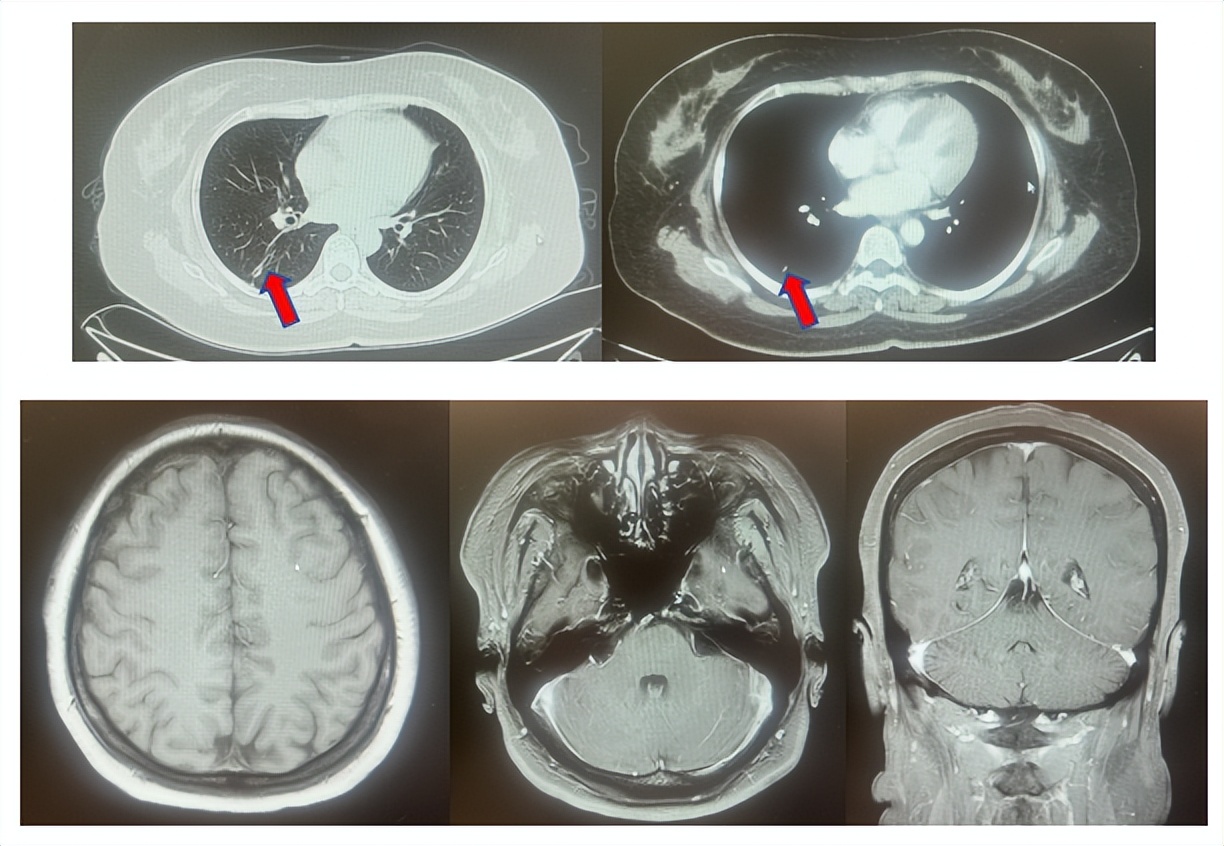

患者符合我科正在开展的“一项比较Durvalumab治疗与标准治疗(含铂化疗)用于PD-L1高表达晚期非小细胞肺癌患者一线治疗的III期随机、开放、多中心研究”的入组要求,经知情同意进入该试验,经随机进入化疗组,于2017年7月至2023年12月应用培美曲塞联合卡铂治疗6周期,后行培美曲塞单药维持治疗105周期,肺内CT现实右肺下叶病灶缩小90%,颅内病灶缩小100%,最佳疗效肺内病灶PR及颅内病灶达CR(图2),于2023年2月复查CT,肺内病灶逐渐增大,至2024年1月,疾病进展出组该临床试验,一线无进展生存为78个月。

图2:上两图分别展示2021年5月患者达到最佳疗效时肺CT肺窗及纵隔窗肺内病灶及肺门淋巴结影像,下三图表示最佳疗效时脑MRI影像